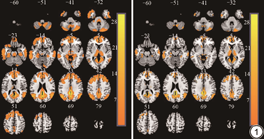

治疗4周后,观察组患者激活脑区数目大于对照组,见图1。

fMRI是在传统MRI技术的基础上发展起来的,相较于传统MRI,其具有更高的时间与空间分辨率,fMRI能够监测患者脑部活动与功能连接情况,且已被证实具有较高的稳定性及敏感度,在大脑激活时神经元活动、能量代谢以及血流动力学反应三者之间存在紧密联系。fMRI可通过测定血流动力学变化从而获得脑激活图像,并以此对脑功能进行评价,其中ALFF值可用于反映脑的功能活动情况。本研究采用fMRI观察老年脑卒中患者记忆功能测评时患侧ALFF值,发现治疗4周后,观察组患者激活脑区数目多于对照组,且观察组患侧fMRI ALFF值高于对照组(P<0.05),推断高频rTMS治疗可能通过改善大脑区域血流、促进神经活动增强发挥促进老年脑卒中患者记忆功能恢复的效果。赵东升等[29]发现,在高压氧治疗的基础上结合rTMS,有利于进一步改善重型颅脑损伤昏迷患者的脑血流参数。KINNEY等[30]指出,rTMS治疗可瞬时增加线圈下区域的脑血流量。上述研究与本文结论类似,均证实了rTMS具有改善脑血流的作用,但本研究首次提出了改善脑血流是该疗法促进脑卒中患者记忆功能恢复的作用机制。